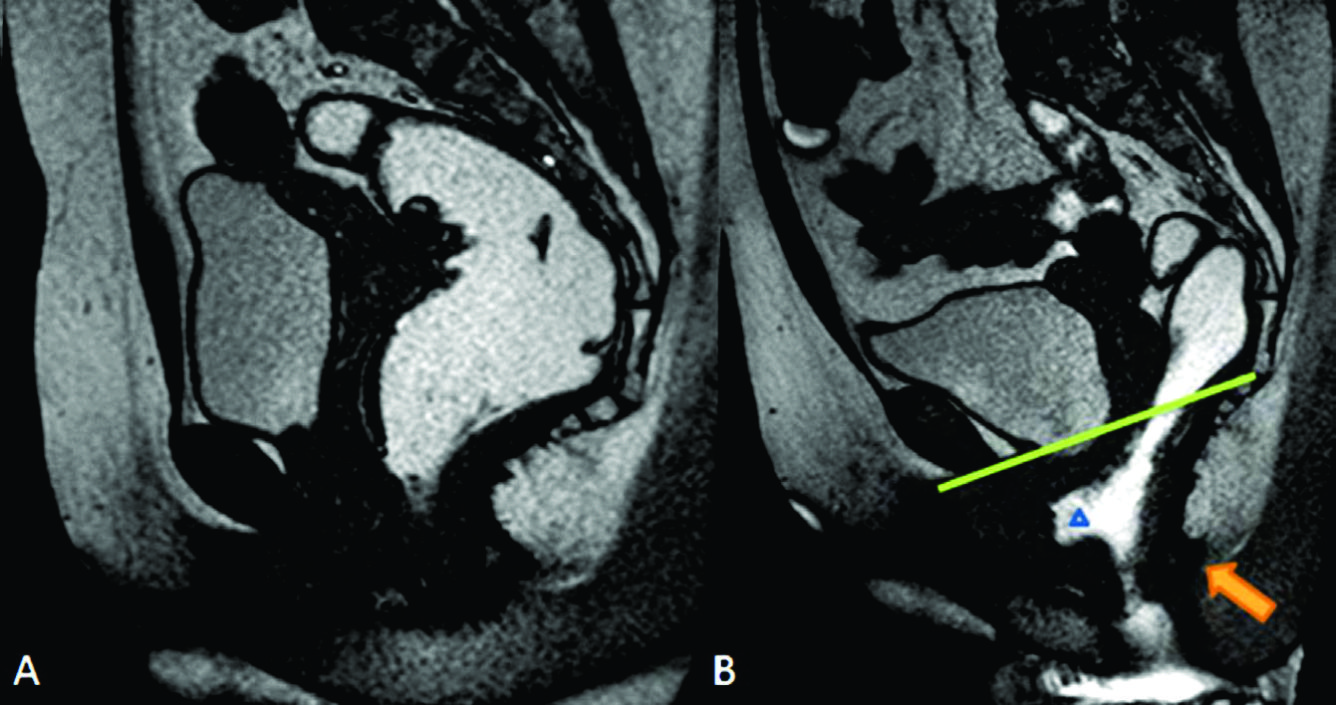

Figura 5

Uterocele.

Imágenes potenciadas en T2 de alta resolución en el plano A) sagital y B) coronal a nivel de la línea media de una mujer durante el reposo. Recto distendido con gel ecográfico tibio (estrella en A). Se observa prolapso de la cúpula vaginal (triangulo en A) y severo uterocele. Véase la herniación de grasa mesentérica (flecha azul en A) y la debilidad de las estructuras de soporte (flechas naranjas en B). Mioma uterino (flecha verde en B).

Los diagnósticos realizados fueron los de cistocele e hipermotilidad de uretra en el compartimento anterior (Ver figuras 6 y 7), histerocele y prolapso vaginal en el compartimento medio (Ver figuras 5, 6, 11 y 13) y sigmoidocele, Douglascele, rectocele y anismo, en el compartimento posterior (Ver figuras 7, 8, 9, 10 y 14).